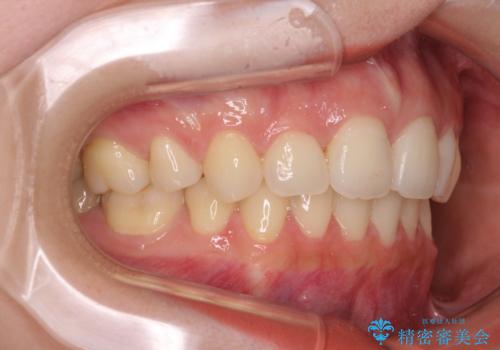

目立たない裏側装置 ハーフリンガルの抜歯矯正

- 口元の突出感を気にして来院された患者様です。

上下左右の第一小臼歯4本を抜歯して口元を下げる治療計画としました。

目立たない装置が希望であったため、上顎が裏側装置である、ハーフリンガル装置を選択されました。